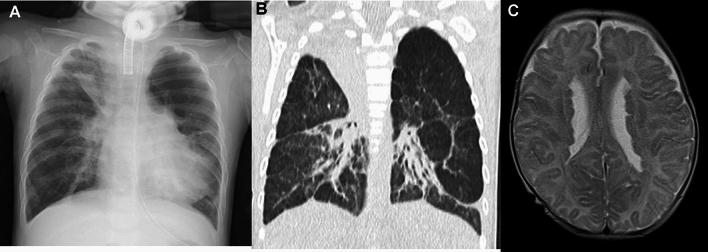

Childhood interstitial lung diseases (chILDs) encompass a diverse group of disorders with a high mortality rate and severe respiratory morbidities. Recent investigations have revealed that the classification of adult ILDs is not valid for chILDs, particularly for ILDs of early onset. Therefore, Children's Interstitial Lung Disease Research Cooperative of North America proposed a new classification of chILDs for affected children under 2 years of age, and later another classification for affected individuals between 2 and 18 years of age. In this review, we provide an overview of the imaging findings of chILDs by classification. Most infantile ILDs have unique clinical, radiological, and molecular findings, while the manifestation of pediatric ILDs overlaps with that of adult ILDs.

儿童间质性肺疾病(chILDs)涵盖了一组具有高死亡率和严重呼吸系统并发症的不同疾病。最近的研究表明,成人间质性肺疾病的分类不适用于 chILDs,特别是对于早发性间质性肺疾病。因此,北美儿童间质性肺疾病研究合作组织提出了一种新的 chILD 分类方法,适用于 2 岁以下的受影响儿童,后来又提出了一种适用于 2 至 18 岁受影响个体的分类方法。在这篇综述中,我们按分类介绍了 chILDs 的影像学表现。大多数婴儿期间质性肺疾病具有独特的临床、放射学和分子表现,而儿科间质性肺疾病的表现与成人间质性肺疾病重叠。